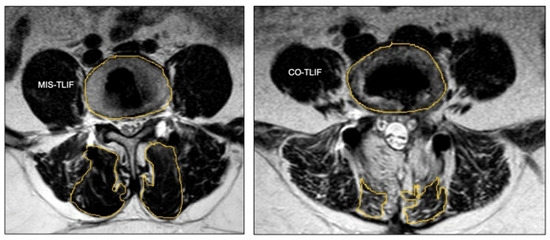

- Fu, C.J.; Chen, W.C.; Lu, M.L.; Cheng, C.H.; Niu, C.C. Comparison of paraspinal muscle degeneration and decompression effect between conventional open and minimal invasive approaches for posterior lumbar spine surgery. Sci. Rep. 2020, 10, 14635. [Google Scholar] [CrossRef] [PubMed]